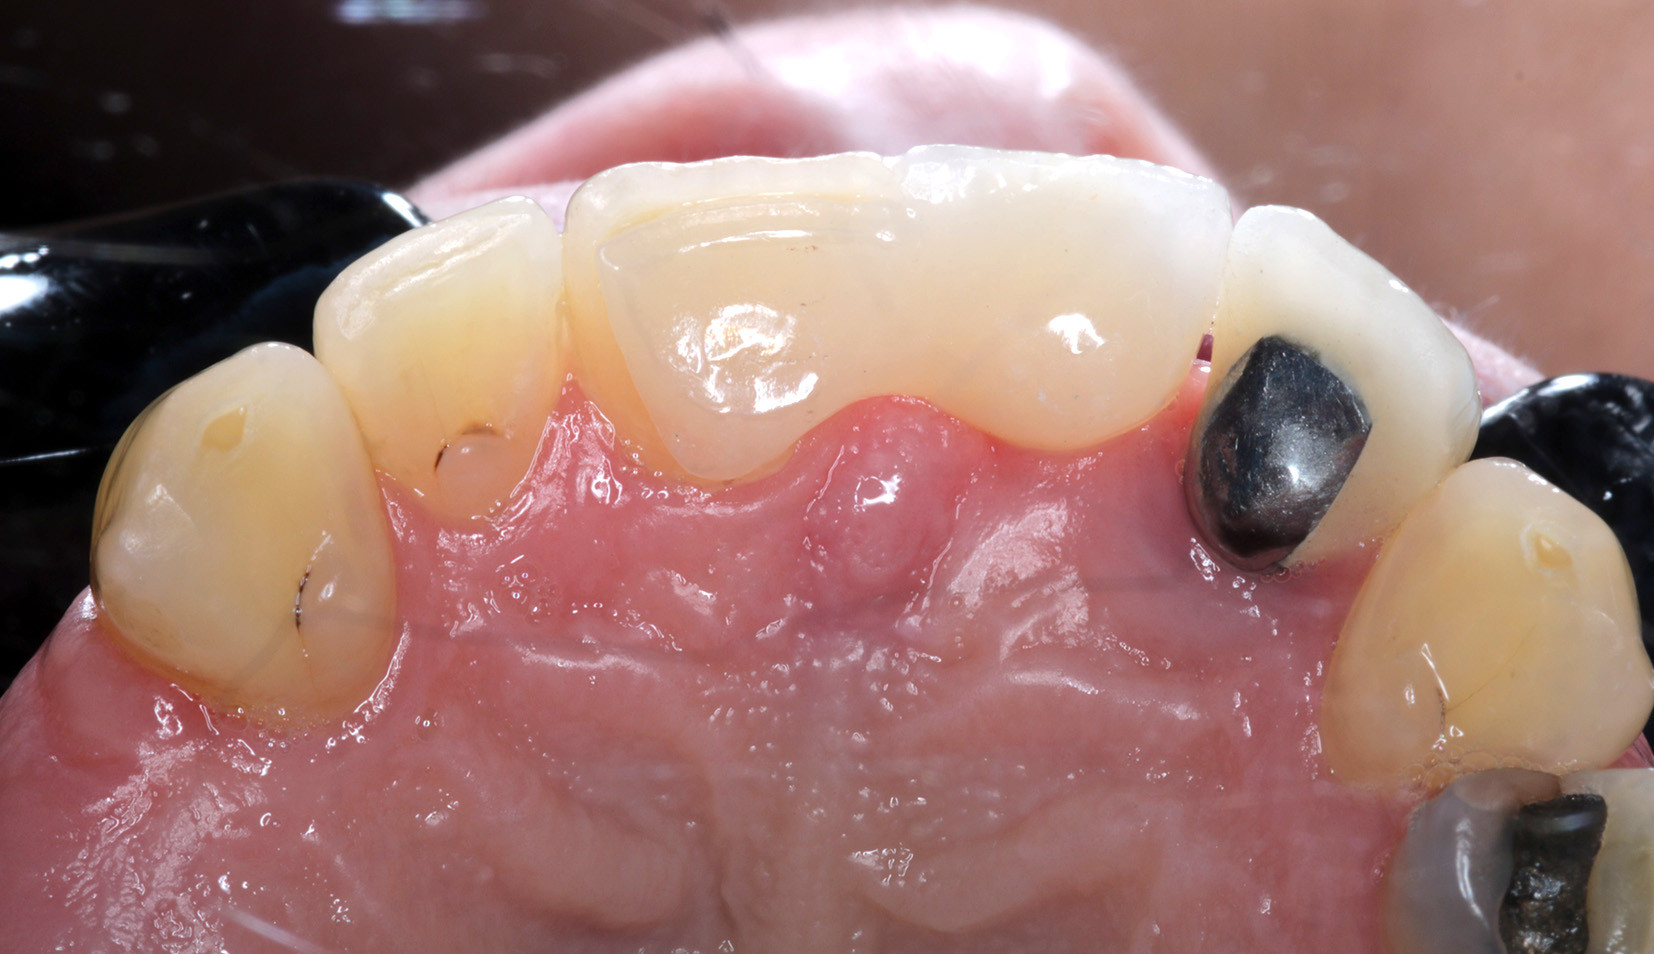

Anish Patel presents a case study that utilises zirconia bonding as an option for a single tooth replacement.